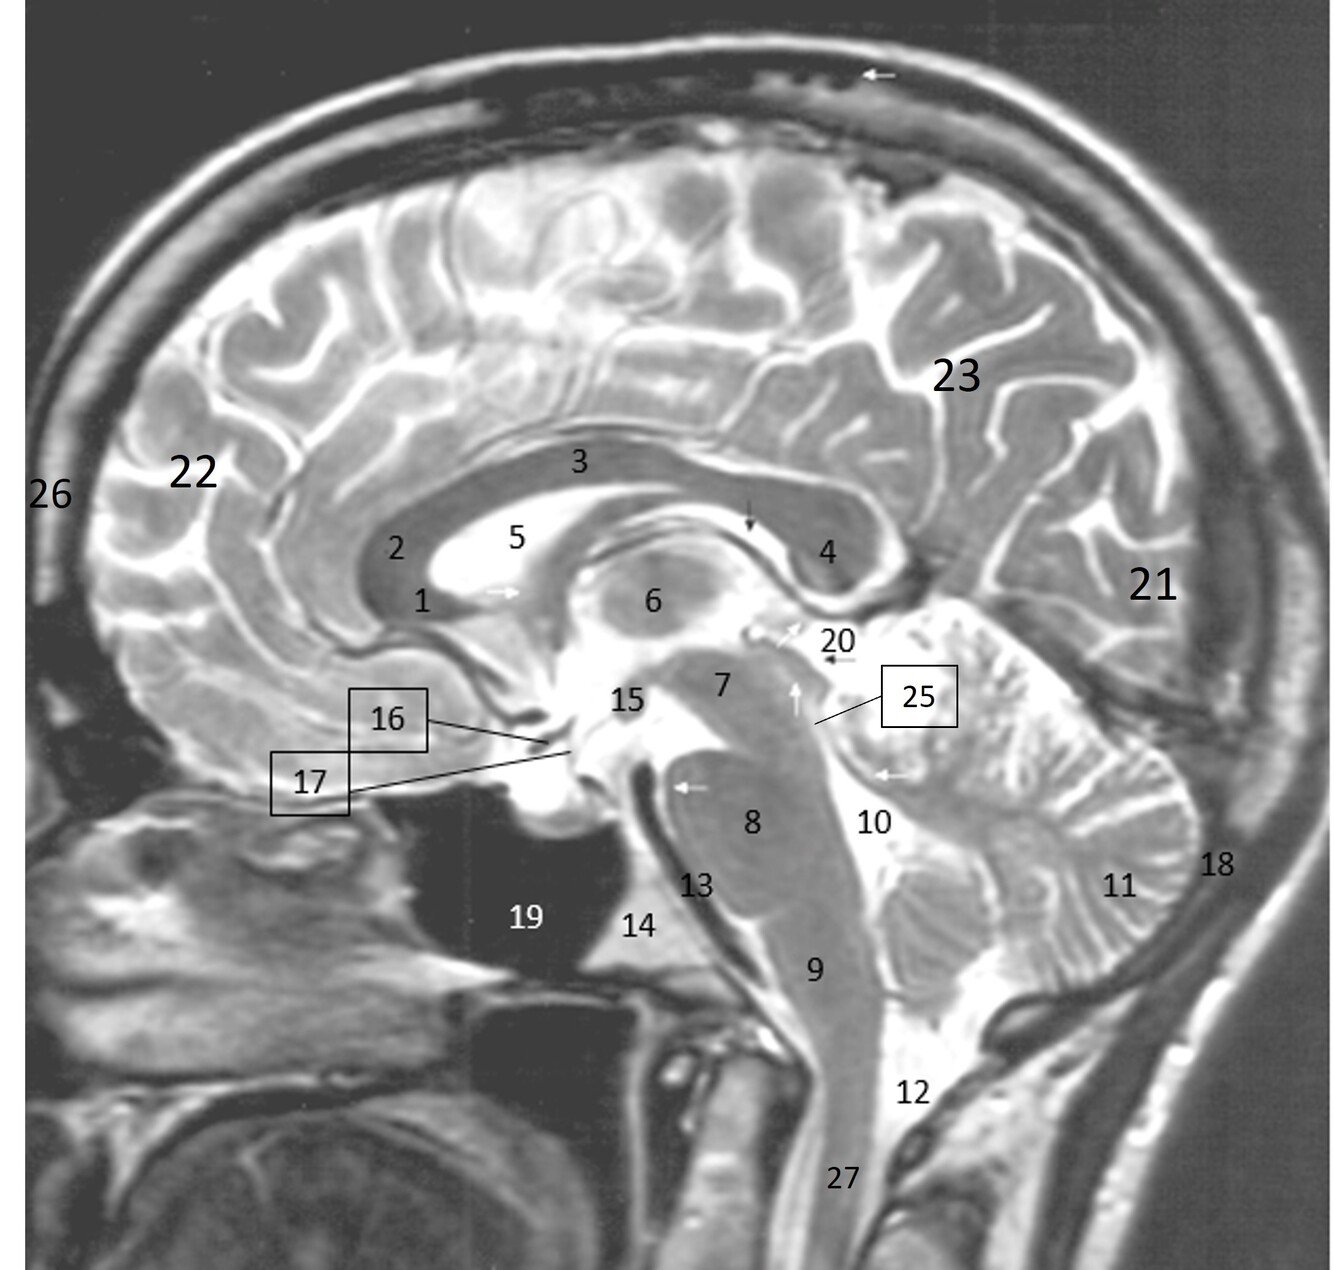

4

Q

Label 1-6

A

1. Rt lateral ventricle

2. Lt caudate nucleus

3. Lt putamen

4. Lt globus pallidus

5. Rt temporal lobe

6. Rt Sylvian fissure

How well did you know this?

5

Label 2,3,4,5,7,8

2=Rt Caudate nucleus

3=Corpus callosum

4=Lt lateral ventricle

5=Third ventricle

7= Septum Pellucidum

8= Rt Interventricular foramen

6

Label 1-4

1. Lentiform nucleus

2. Caudate nucleus

3. Lateral ventricle

4. Cerebellum

7

1. Head of Caudate nucleus

2. Lateral ventricle

3. Thalamus

10

Label 1,3,4,5,7

1=3rd ventricle

3-Anterior commissure

4=Pineal gland

5=Choroid plexus

7=Posterior commissure

11

Label 4,5,6,8,9

4=Genu, CC

5=Lt lateral ventricle (body)

6=Head of Rt caudate nucleus

8-Rt Lentiform nucleus

9=Lt lateral ventricle (post. horn)

12

Label 2,18,19,21

2=Rt internal capsule

18=Frontal sinus

19=Septum pellucidum

21=Lt external capsule

13

Label 3,5,7,10,11,12,14,20

3=Lt frontal lobe

5=Lt Lentiform nucleus

7=Lt internal capsule

10=Insula

11=Lt Claustrum

12=Rt Thalamus

14=Splenium, CC

20=Lt Interventricular foramen

14

Label 1-9

1=Rostrum (CC)

2-Genu (CC)

3-Body (CC)

4=Splenium (CC)

5=Lateral ventricle

6=Thalamus

7=Midbrain

8=Pons

9-Medulla oblongata

15

Label 10-18

10-4th ventricle

11=Cerebellum

12=Cisterna Magna

13=Basilar artery

14=Clivus

15-Mamillary body

16=Optic chiasm

17=Infundibulum

18=Occipital bone

16

Label 19-27

19=Sphenoid sinus

20=Quadrigeminal cistern

21=Occipital lobe

22-Frontal lobe

23-Parietal lobe

25-Cerebral aqueduct

26-Frontal bone

27-Spinal canal